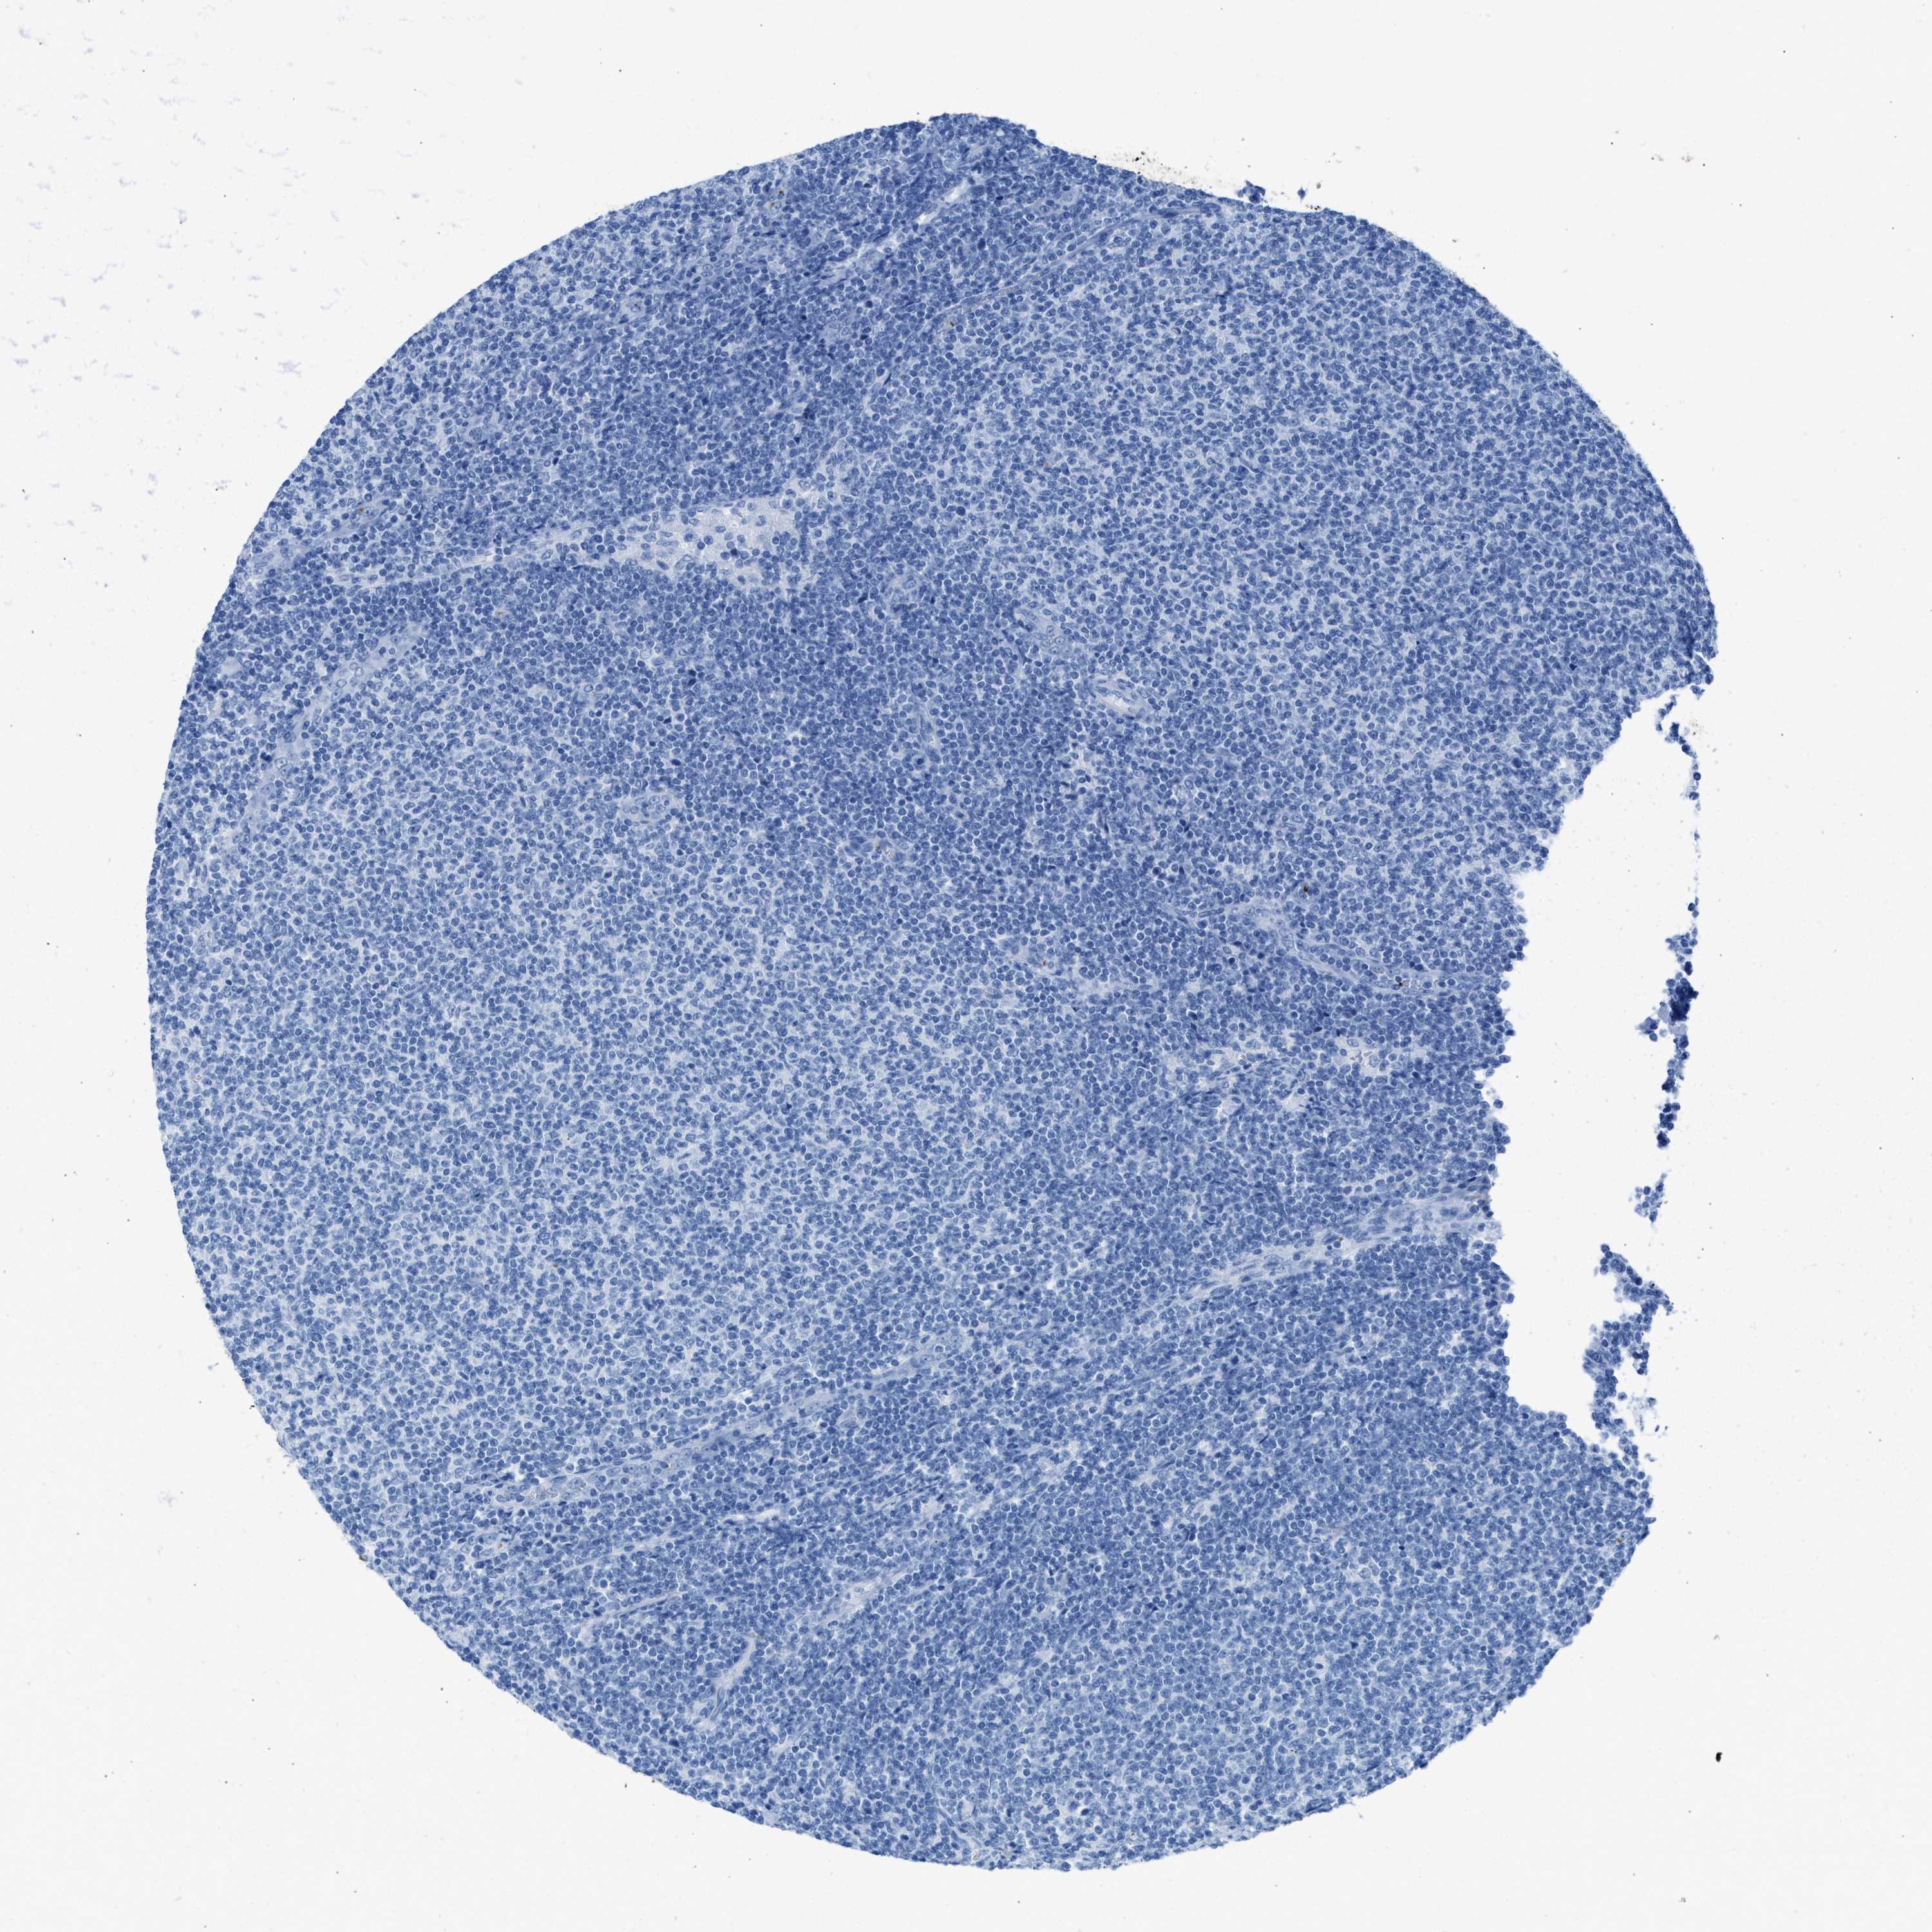

LYMPHOMA - Protein expressioni

A mouse-over function shows sample information and annotation data. Click on an image to view it in a full screen mode. Samples can be filtered based on level of antibody staining by selecting one or several of the following categories: high, medium, low and not detected. The assay and annotation is described here.

Antibody stainingi

Antibody staining in the annotated cell types in the current human tissue is reported as not detected, low, medium, or high, based on conventional immunohistochemistry profiling in selected tissues. This score is based on the combination of the staining intensity and fraction of stained cells.

Each image is clickable and will lead to virtual microscopy that enables deeper exploration of all samples and also displays staining intensity scores, fraction scores and subcellular localization as well as patient and tissue information for each sample.

Antibody HPA018790

Hodgkin's disease, NOS

Malignant lymphoma, non-Hodgkin's type, High grade

Malignant lymphoma, non-Hodgkin's type, Low grade